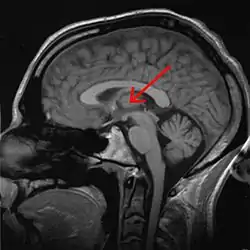

Thalamus

The thalamus (from Greek θάλαμος, "chamber")[1] is a large mass of gray matter located in the dorsal part of the diencephalon (a division of the forebrain). Nerve fibers project out of the thalamus to the cerebral cortex in all directions, allowing hub-like exchanges of information. It has several functions, such as relaying of sensory signals, including motor signals to the cerebral cortex[2][3] and the regulation of consciousness, sleep, and alertness.[4]

Anatomically, it is a paramedian symmetrical structure of two halves (left and right), within the vertebrate brain, situated between the cerebral cortex and the midbrain. It forms during embryonic development as the main product of the diencephalon, as first recognized by the Swiss embryologist and anatomist Wilhelm His Sr. in 1893.[5]

The thalamus is a paired structure of gray matter located in the forebrain which is superior to the midbrain, near the center of the brain, with nerve fibers projecting out to the cerebral cortex in all directions. The medial surface of the thalamus constitutes the upper part of the lateral wall of the third ventricle, and is connected to the corresponding surface of the opposite thalamus by a flattened gray band, the interthalamic adhesion. The lateral part of the thalamus is the phylogenetically newest part of the thalamus (neothalamus), and includes the lateral nuclei, the pulvinar and the medial and lateral geniculate nuclei.[6][7] There are areas of white matter in the thalamus including the stratum zonale that covers the dorsal surface, and the external and internal medullary laminae. The external lamina covers the lateral surface and the internal lamina divides the nuclei into anterior, medial and lateral groups.[8]